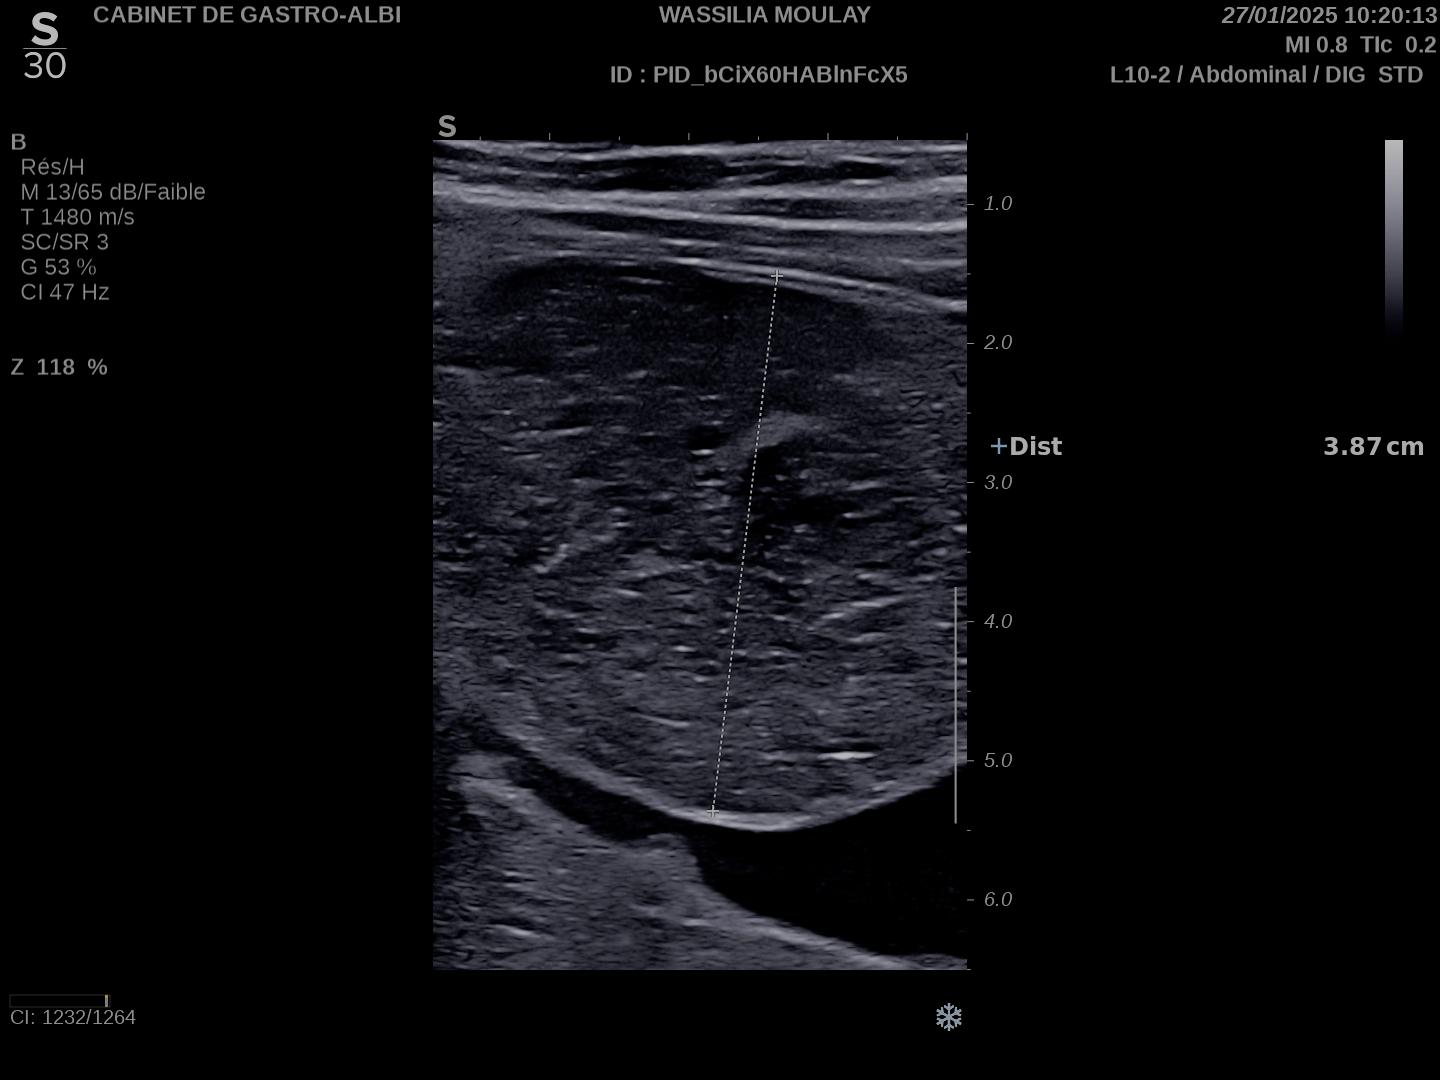

L'occlusion du grêle est très facile à voir en échographie

On peut voir en cas d'occlusion:

Sténose serrée